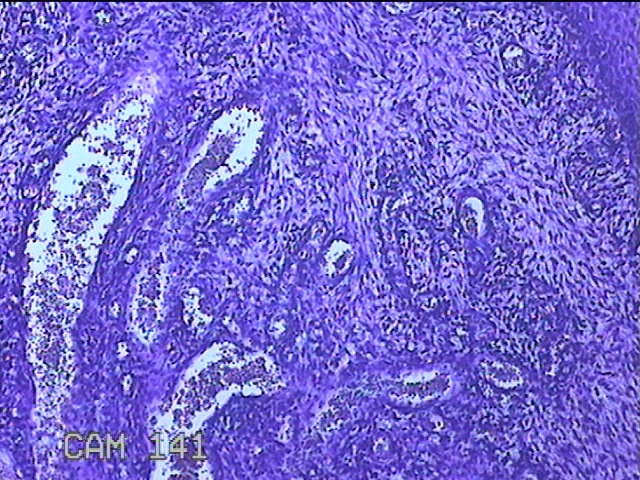

宫颈赘生物

性别

女

年龄

49岁

临床诊断

人乳头瘤病毒感染

一般病史

宫颈HPV阳性TCTLSLL

标本名称

大体所见

灰白粉红色肿物1.2x0.8x0.2cm两个,表面光滑。

图2